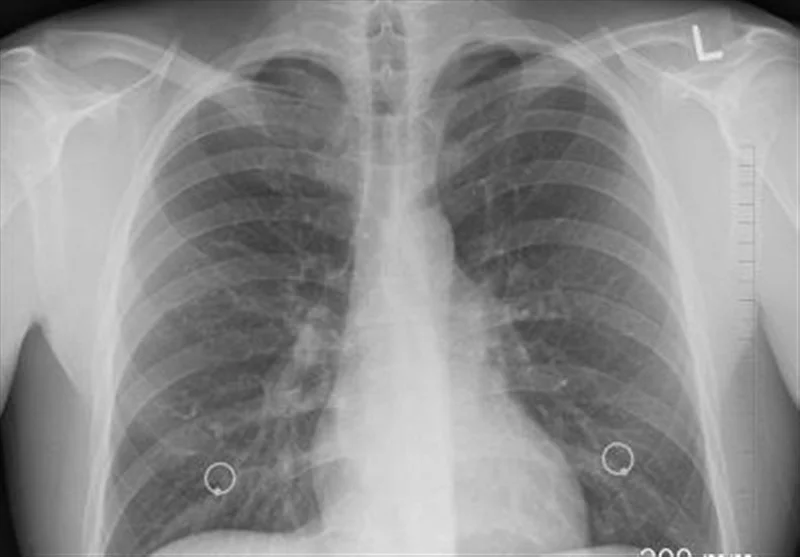

افزایش نگران‌کننده سرطان ریه در گلستان؛ تریاک چگونه 3.6 برابر خطر را بیشتر می‌کند؟

آمار جدید نشان می‌دهد که مصرف تریاک در گلستان خطر ابتلا به سرطان ریه را تا 3.6 برابر افزایش می‌دهد؛ موضوعی که زنگ هشدار جدی برای سلامت عمومی این استان است.

وی خاطرنشان کرد: مصرف منظم تریاک، خطر ابتلا به سرطان ریه را 3.6 برابر افزایش می‌دهد و در صورت مصرف همزمان تریاک و سیگار، خطر ابتلا به 13 برابر می‌رسد. افرادی که دو بار یا بیشتر در روز تریاک مصرف می‌کنند، 9 برابر بیشتر در معرض خطر هستند.

روشندل با اشاره به اینکه تریاک دارو نیست و یک ماده سرطان‌زاست، بیان کرد: این پژوهش نشان داد که اثر مخرب تریاک در زنان بارزتر است و خطر ابتلا در آنها 7 برابر افزایش می‌یابد. خطر آن به تنهایی بسیار بالاست و مصرف مشترک با سیگار، خطر را به طور نجومی افزایش می‌دهد.

وی عنوان کرد: سرطان ریه یکی از پنج سرطان کشنده در جهان است. به دلیل تهاجمی بودن، زمان کمی برای درمان باقی می‌گذارد و متاسفانه بسیاری از بیماران در سال‌های اول فوت می‌کنند. میزان ابتلا در بخش مردان حدود 12.7 در هر صد هزار نفر و در میان زنان رقمی کمتر از مردان است. در استان گلستان اما میزان شیوع این بیماری بالاتر است و در مردان میزان ابتلا 21.3 در هر صد هزار نفر (بسیار بالاتر از میانگین کشوری) و در میان زنان 5.21 در هر صد هزار نفر است.

روشندل با اشاره به عوامل خطر شناخته شده سرطان ریه گفت: مصرف سیگار (ریسک بسیار بالا)، در معرض دود سیگار بودن، مصرف الکل و نوشیدنی‌های الکلی، مواجهه شغلی با تشعشعات (مثل برخی محیط‌های بیمارستانی یا صنعتی)، آلودگی هوا و آب، تریاک (به عنوان یک عامل خطر مهم و خاص در کشور) است.